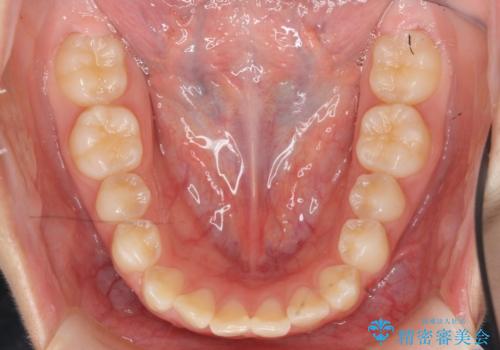

インビザラインで行う八重歯の治療

- 笑った時に目立つ八重歯の矯正治療を求めて来院されました。

マイクロインプラントを用いた臼歯の後方牽引、およびゴムかけ等の付加処置を駆使して八重歯の治療を行っていきます。

しっかりとゴムかけを頑張っていただいたおかげで、上顎臼歯の後方移動が達成されしっかりとした噛み合わせの構築と、八重歯の治療を達成することができました。